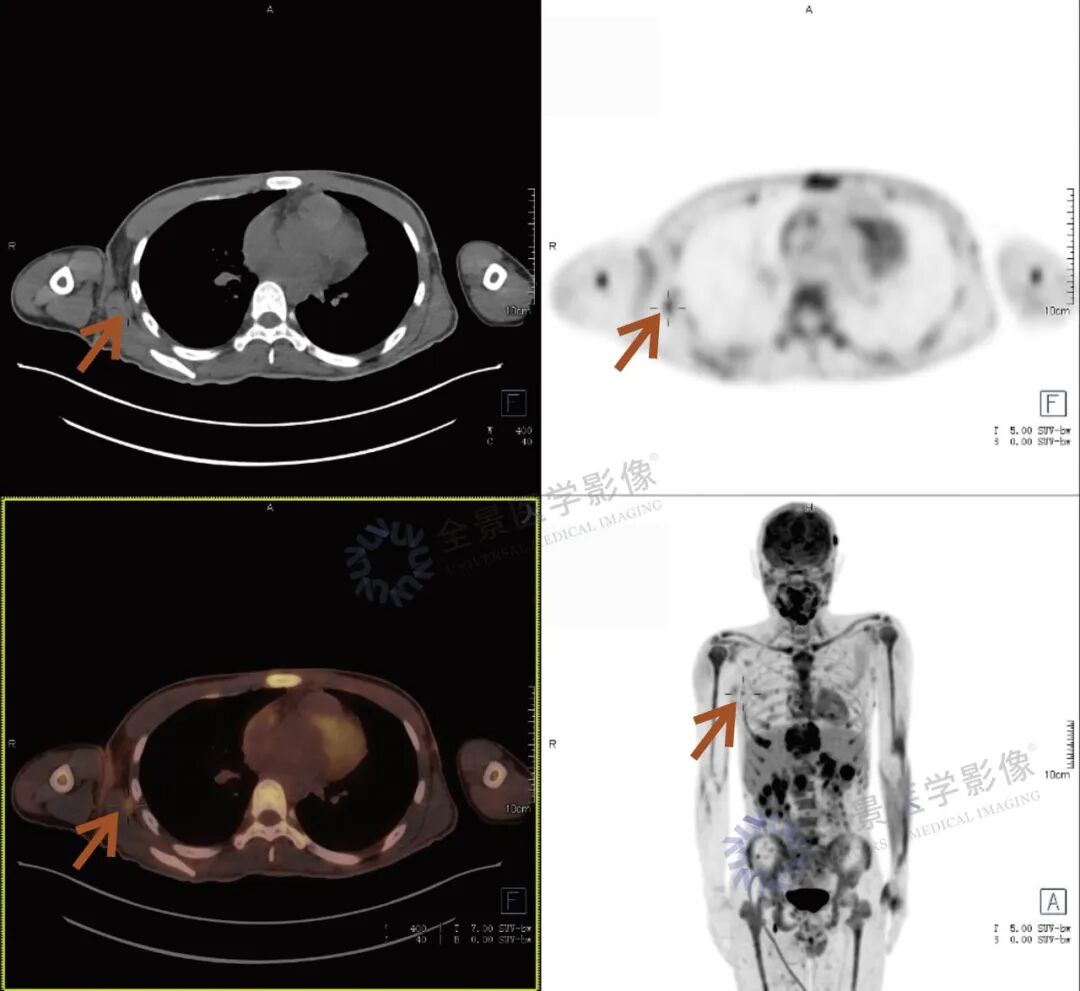

张先生(化名),因持续3个多月的腹痛、腰痛在外院就诊。初始CT检查发现其胸11椎体骨质破坏伴周围软组织肿胀,考虑为“脊柱结核”等感染性病变,并接受了中药治疗。然而,两个月后,张先生又出现了新的症状——牙痛。 经病理活检及免疫组化检查,最终确诊为极为罕见的Erdheim-Chester病。为全面评估这一可累及全身多系统疾病的侵犯范围、明确病灶活动性,并为制定精准治疗方案提供依据,张先生进行了全身PET/CT检查。 PET/CT检查图像: PET/CT检查结果: (1)中轴骨及四肢骨广泛FDG代谢活跃伴信号异常;其中胸10、胸11椎体病灶周围软组织增厚,累及邻近椎管内及双侧椎间孔、双侧胸膜,并与主动脉分界不清。 (2)全身皮下及肌层内多发结节及肿块,FDG代谢活跃;全身软组织广泛肿胀。 (3)鼻咽各壁增厚,顶后壁为著,FDG代谢活跃。 (4)甲状腺多发结节,FDG代谢活跃;双肾及胰腺多发结节及肿块,FDG代谢活跃;双侧阴囊内异常信号伴FDG代谢活跃; (5)左侧锁骨上窝、纵隔内(2L区、3A区)、降主动脉旁、左侧横膈前组、右侧腋窝、左肾周间隙、肠系膜区、双侧髂血管旁多发淋巴结,FDG代谢活跃; (6)心包局部呈结节状稍增厚,FDG代谢轻度活跃; 综上,结合临床,均考虑Erdheim-Chester病所致。 此次PET/CT不仅证实了已知的脊柱病变,更一次性揭示了临床尚未怀疑的、广泛存在于内脏、淋巴结及软组织的隐匿病灶,为疾病分期与治疗提供了决定性依据。